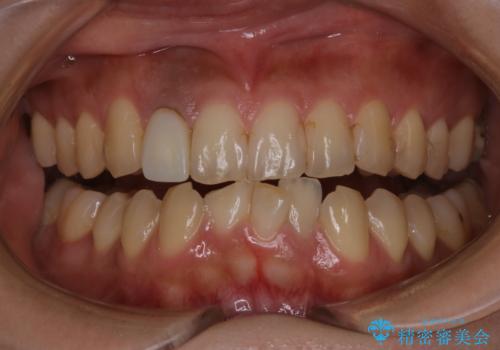

前歯のセラミック作成前にオフィスホワイトニング

- 前歯のセラミックを作る前に、ホワイトニングで全体を白くしたいとのことでした。

効果をより高めるために処置前クリーニング(¥3300)を行ってから、オフィスホワイトニングのエクセレントコース(¥29700)を行いました。

- ¥33000費用は治療当時の料金となります